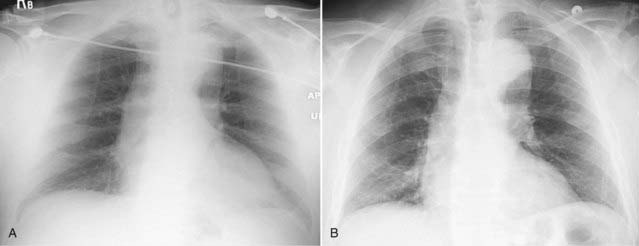

Figure 2-3 The spine sign.

Frontal (A) and lateral (B) views of the chest demonstrate airspace disease on the lateral film (B) in the left lower lobe that may not be immediately apparent on the frontal film (look closely at A and you may see the pneumonia in the left lower lobe behind the heart). Normally, the thoracic spine appears to get “blacker” as you view it from the neck to the diaphragm because there is less dense tissue for the x-ray beam to traverse just above the diaphragm than in the region of the shoulder girdle (see also Fig. 2-2). In this case, a left lower lobe pneumonia superimposed on the lower spine in the lateral view (solid white arrow) makes the spine appear “whiter” (more dense) just above the diaphragm. This is called the spine sign. Note that on a well-positioned lateral projection, the right and left posterior ribs almost superimpose on each other (solid black arrow), a sign of a true lateral.